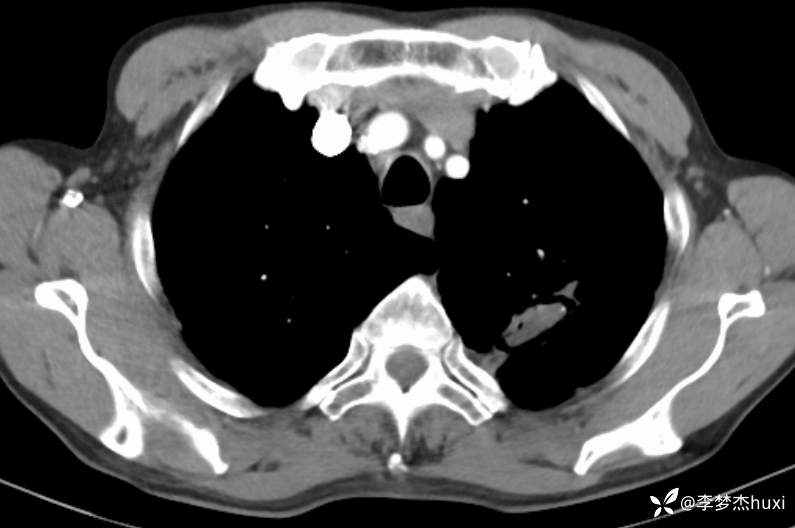

1.现病史:患者老年 男,患者于入院前7天“感冒”后出现咳嗽、咳痰,为白痰,不易咳出,伴胸闷憋气,活动后加重,病初发热,最高达38.0℃,无胸痛,无咯血,无腹痛、腹泻,无恶心、呕吐,无尿频、尿急、尿痛,院外给予口服药物(自诉口服药物,具体药物名称不详)治疗,病情无明显好转,6-13于我院门诊查胸部CT:左肺上叶软组织密度影-性质待定,双肺炎症,双肺气肿,双肺大泡,双肺部分实性结节-炎症?双肺实性结节,主动脉及冠状动脉钙化,双侧胸膜局限性增厚;肝脏多发囊性病变。6-14查胸部增强CT:左肺上叶空洞-真菌感染?占位不除外;双肺炎症,双肺气肿,双肺大泡,双肺部分实性结节-考虑炎症,双肺实性结节,主动脉及冠状动脉钙化,双侧胸膜局限性增厚;肝脏多发囊性病变;今日为进一步诊治来我院;门诊以“肺空洞”收入院。